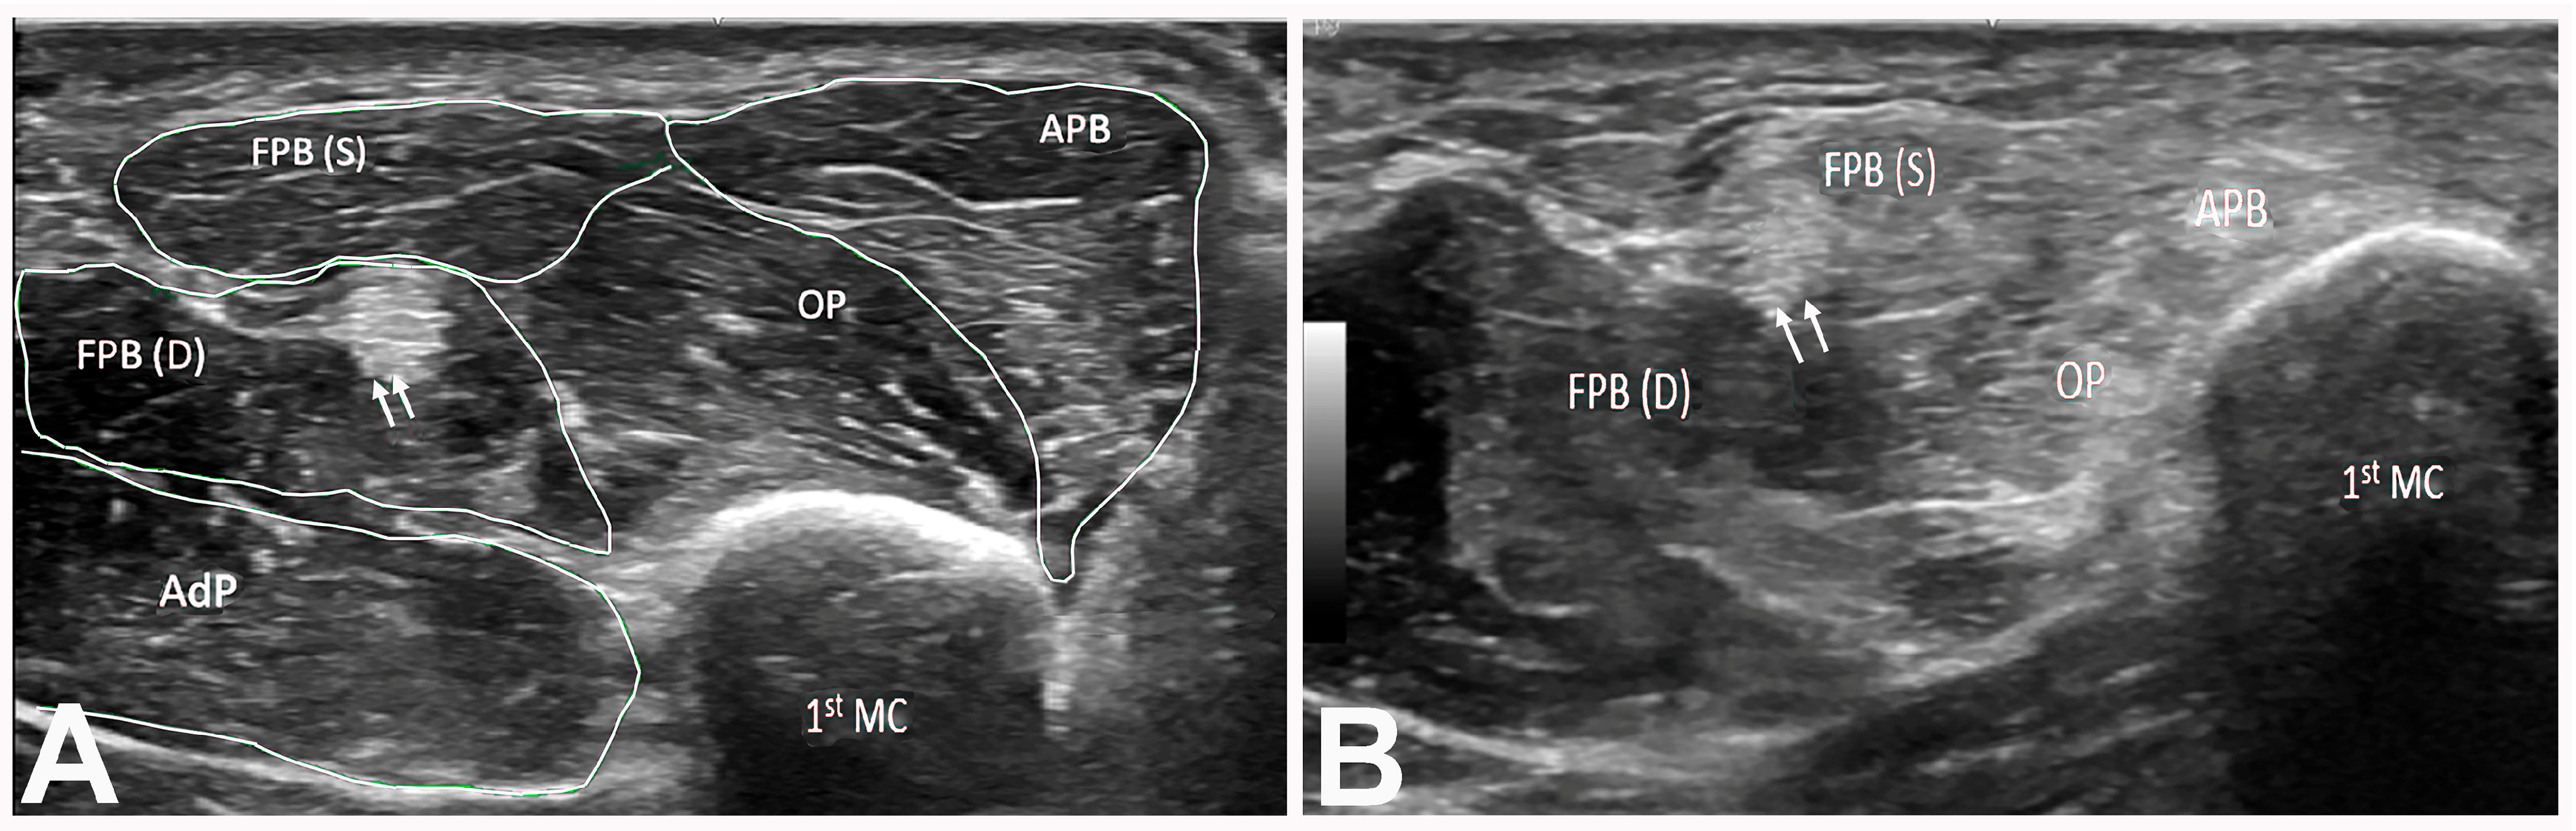

| Type of Thenar Atrophy | Description | Mechanism |

|---|---|---|

| Total | APB, OP, and FPB muscles are atrophic, leading to a “flat” thenar eminence | 1. Severe CTS: median nerve innervates all thenar muscles, including both heads of the FPB muscle |

| 2. Severe CTS and ulnar neuropathy causing atrophy of all thenar muscles, including both heads of the FPB muscle | ||

| 3. T1 radiculopathy causing atrophy of all thenar muscles, including both heads of the FPB muscle | ||

| Partial | APB and OP muscles are atrophic with an intact FPB muscle visible in the distal/medial part of the thenar eminence | 1. Severe CTS with intact deep head of the FPB (innervated by the ulnar nerve) |

| 2. Severe CTS with an intact FPB muscle due to ulnar innervation of both heads | ||

| Partial with hypertrophy of the FPB | APB and OP muscles are atrophic, causing the lateral part of thenar eminence to be flat with a prominent “bulge” on the medial aspect from a large FPB muscle | Severe CTS with an intact FPB muscle compensating for the loss of the OP muscle; more likely when the FPB muscle is entirely supplied by the ulnar nerve |